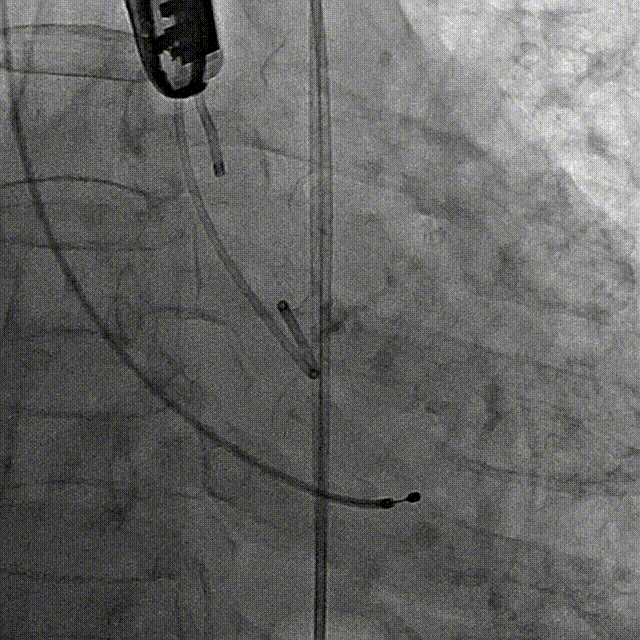

5、调整至共平面角度,在加硬导丝支撑下,成功跨瓣;

6、造影确定瓣膜到位,180bpm快速起搏下精准释放瓣膜;

7、撤出输送系统,根部造影结果显示瓣膜释放后形态位置良好、无瓣周漏,且左右冠脉均显影正常,冠脉血流未受影响;